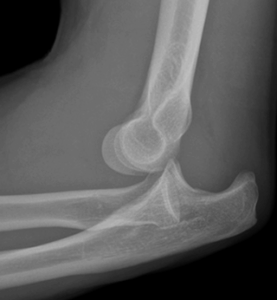

Elbow dislocation is the second most common large joint dislocation in adults, occurring when the bones of the forearm (radius and ulna) separate from the upper arm bone (humerus). Posterior dislocations, where the forearm bones move backward relative to the humerus, account for the majority of cases. These injuries typically result from falls on an outstretched hand.

Emergency evaluation includes physical examination to assess neurovascular status (pulses, sensation, and motor function) and imaging studies. X-rays confirm the dislocation and identify any associated fractures. In cases where vascular injury is suspected, additional imaging such as angiography may be necessary.